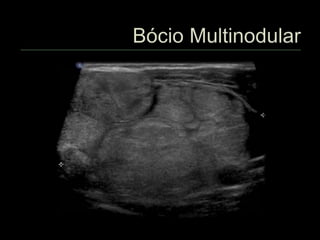

 Bócio nodular

 Multinodular